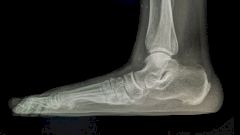

Плоскостопие развивается интересным образом. Своды стопы проседают, уплощаются. Если показывать на макете, то механизм развития плоскостопия происходит примерно следующим образом: когда человек стоит, то пяточная кость стопы у него уходит под нагрузкой вбок.

Плоскостопие развивается тогда, когда связочный аппарат недостаточно жесткий или передаются по наследству особенности соединительной ткани. Она эластичная, даже слишком эластичная и тянется. Есть такие стопы — будто гуттаперчевые, когда их осматриваешь. Когда пятка слишком сильно уходит в эту сторону, получается, что вся стопа провисает и развивается плоскостопие — то есть уплощение свода стопы. Когда это происходит? Это очень частая проблема детей. Но нужно понимать, что все дети рождаются с плоскостопием. Своды стопы формируются, только когда ребенок начинает ходить: в этот момент они начинают немного подниматься. Но это происходит не у всех.